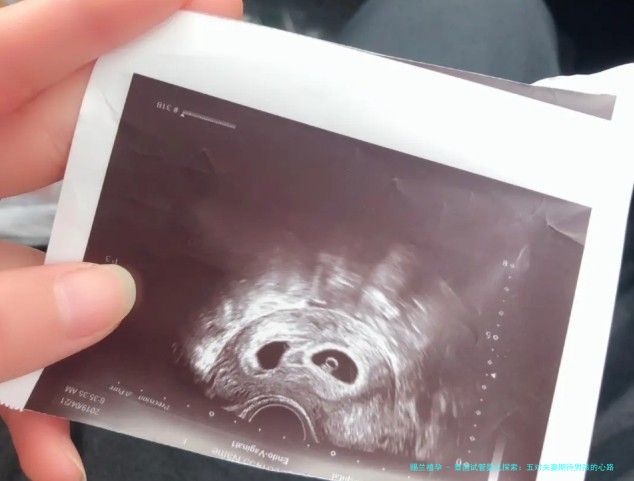

在这个满怀期待与挑战的路程中,我们注意五对来自不同背景的中国夫妇,他们选择泰国进行试管婴儿(试管婴儿(IVF))治疗,等待能够拥有一个男娃。这个决意后背,就是他们对家庭、守旧和将来的深刻思考。

这五对夫妇的故事,是关于愿望、挑战和盼望的事迹。他们其中有的人因为遗传疾病,某些人因为传统观点,再有的人因为对家庭的渴想。

张氏夫妇,他们的第1个孩子患有稀有的遗传病,为了减低第二个孩子抱病的风险,他们选择到泰国进行性别选择,以确保随后一个孩子是健康的男孩。